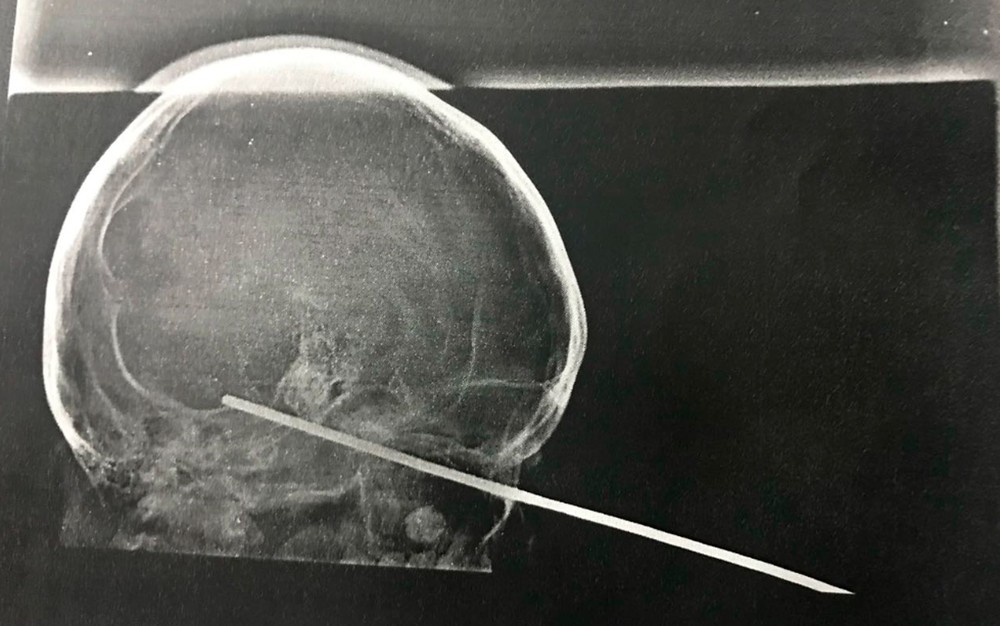

Segundo o G1 Bahia, uma foto do raio-x da face da criança foi divulgada pelo hospital e mostra a posição do espeto na cabeça do garoto.

De acordo com a Santa Casa de Misericórdia de Itabuna, que administra a unidade, o objeto passou pelo seio cavernoso e ficou no tronco encefálico.